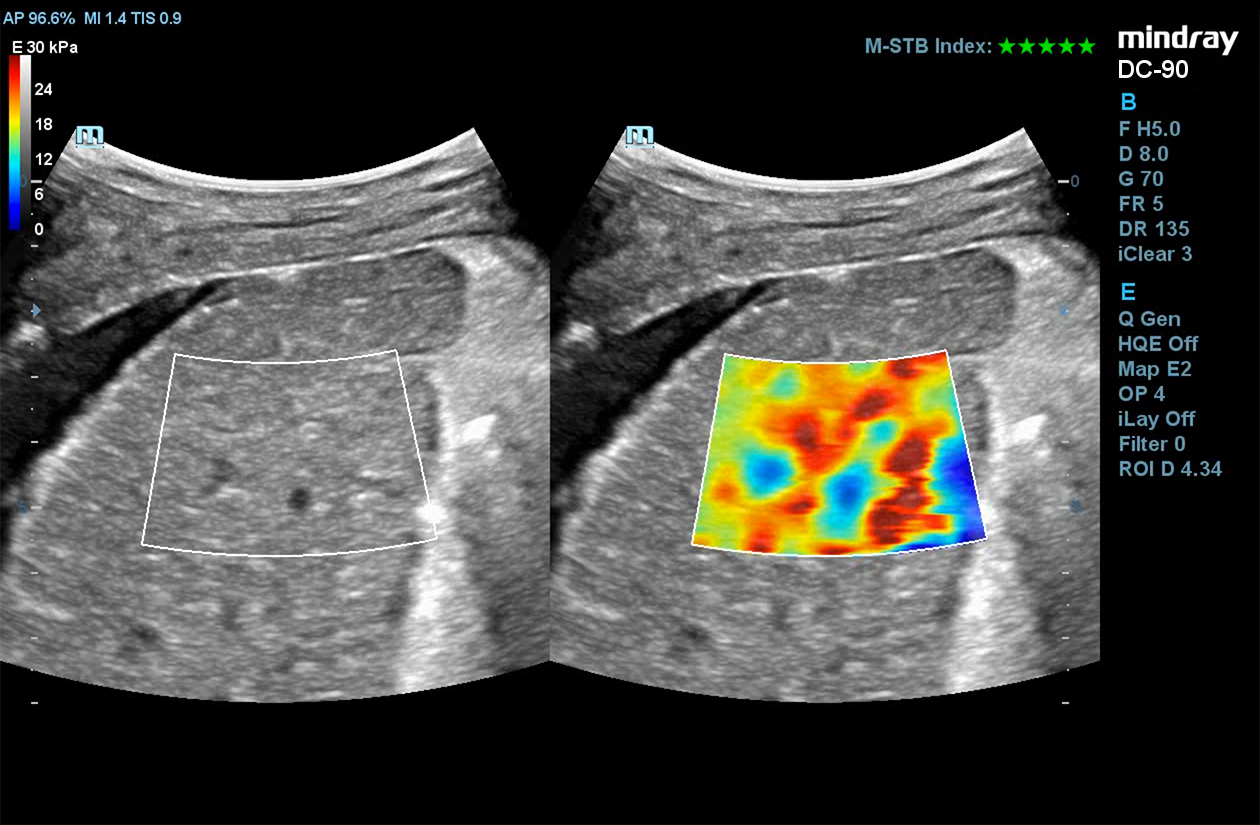

STE

Mindray’s Sound Touch Elastography (STE) utilizes exclusive Ultra-Wide Beam Tracking technology to provide comprehensive quantification metrics and dynamic visual display of tissue stiffness for enhanced diagnostic confidence. Using real-time and rapid data acquisition from a wide beam single pulse, STE is designed to reduce noise caused by motion artifact for improved efficiency and accuracy of measurements.